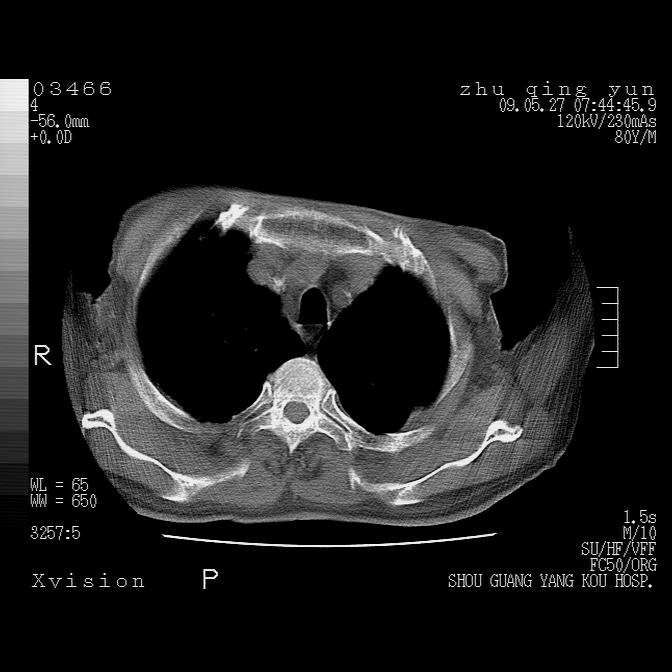

病人男性,年龄80,气喘来院,其他病史不太详细,1月前有过恶心,呕吐,在当地人民医院做过钡餐,诊断胃炎,

1)考虑左肺中央型肺癌并阻塞性肺炎,后下纵隔受侵伴纵隔淋巴结转移。2)双侧少量胸腔积液,胸膜增厚。3)心包积液。

左肺下叶见多发片状及结节状病灶,左肺基底段支气管闭塞,纵隔内见多发淋巴结肿大,纵隔向左侧移位,左侧胸廓变小。应该是左肺下叶中心型肺癌,纵隔淋巴结转移,左侧肺内转移,左肺基底段肺不张,阻塞性肺炎。

1)考虑左肺中央型肺癌并左肺下叶阻塞性肺炎、不张;左胸膜腔积液、心包积液、纵隔淋巴结转移;癌肿累及左心房。2)左心室大。冠状动脉壁钙化斑。